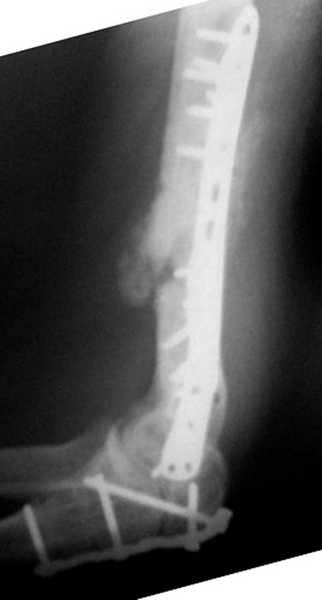

Второй случай, также после множественных операций:

пластина, аппарат, серкляж и парез нерва.

Также ревизия, из-за низкого состояния доступ был

сделан через остеотомию локтевого отростка.

Ложный сустав фиксирован двумя локинг плейт с

аутокостной пластикой, также через два месяца увидели признаки консолидации.

Движение в суставе разрешили в две недели.